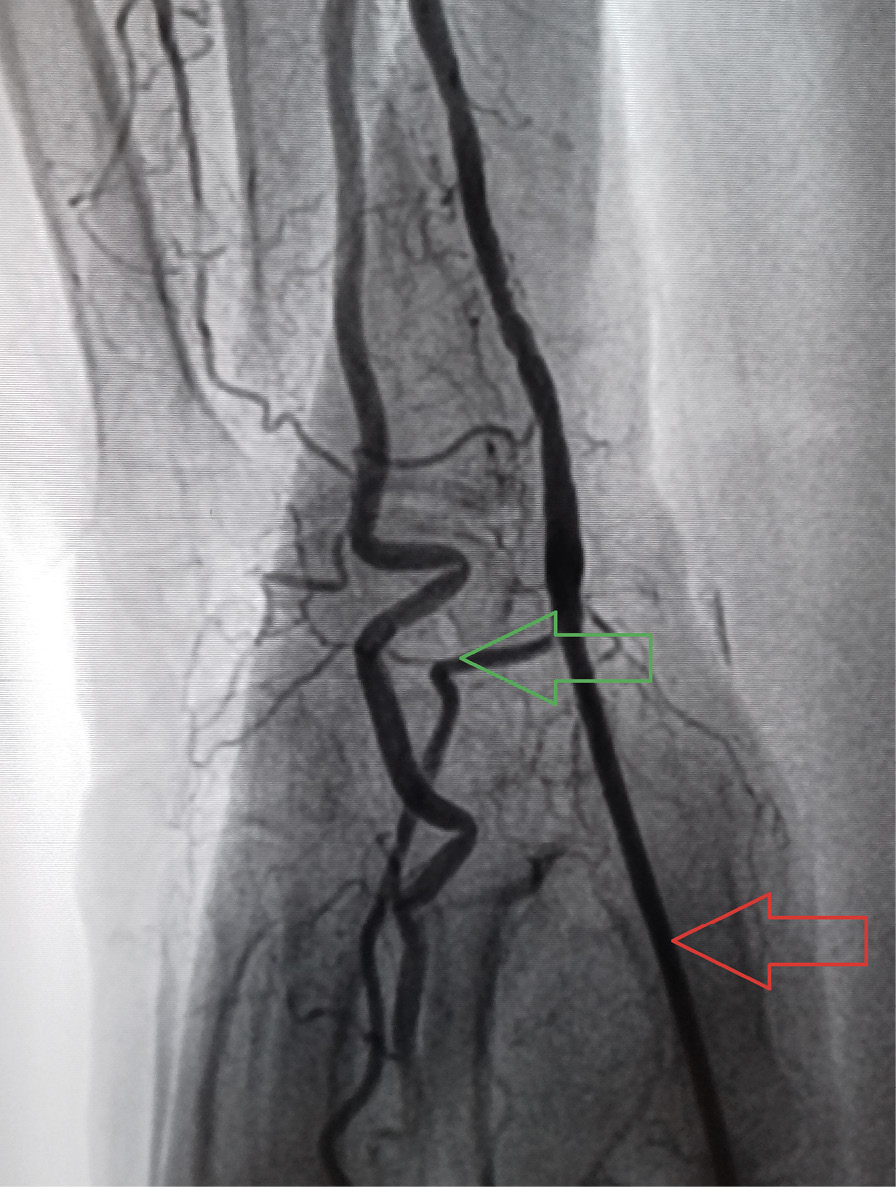

Рис. 2. Дорсопальмарный (модифицированный дистальный) лучевой доступ: контрольная ангиография доступа (красной стрелкой указана область пункции лучевой артерии, зеленой стрелкой – поверхностная ладонная ветвь лучевой артерии r. superficialis)

Рис. 4. Окклюзия дистальных отделов лучевой артерии по данным выполненного на 5-е сутки ультразвукового исследования артерии доступа (указана красной стрелкой), кровоток в поверхностной ладонной ветви лучевой артерии (указана зеленой стрелкой) сохранен [17]